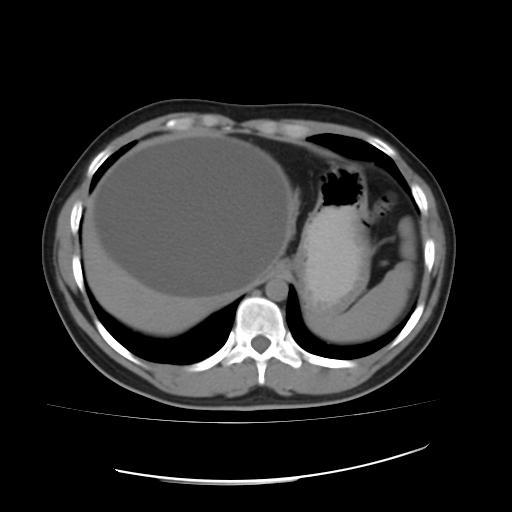

肝包虫(泡状棘球蚴)_手机搜狐网

典型肝囊虫病

图1为肝囊型包虫病(ce)1型,ct平扫显示肝右叶类圆形水样密度病灶,囊壁